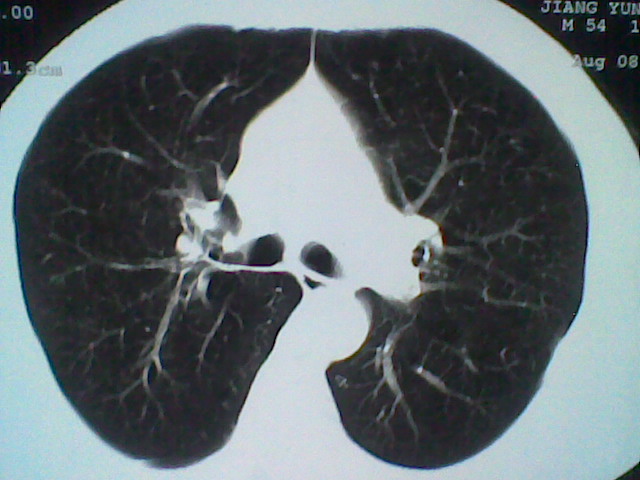

标题: CT21512:支扩伴感染?

患者女。咳嗽数天,咯血半天。

我们报的是支扩伴感染?